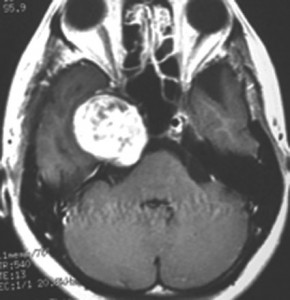

開頭手術で摘出した方がよい三叉神経鞘腫

この腫瘍もちょっと大きいので放射線治療だけで治すことは難しいでしょう。この三叉神経鞘腫は少し大きいかなと思うくらいの大きさです。 脳幹部が圧迫されていますから手術摘出した方がいい例です。これも側頭部の前の方の骨を開頭するだけで全部取れます。